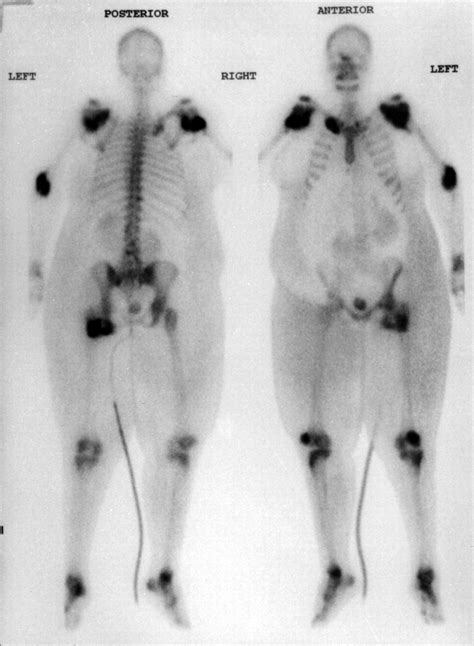

HETEROTOPIC VIEW